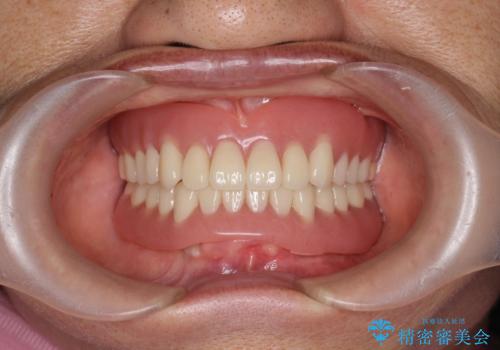

- 他院にて入れ歯を入れたが全体的に左に傾いており、咬みにくく、見た目も気になるといらっしゃった方の症例です。

診査の結果、虫歯が進行し保存できない歯が多かったため抜歯し、磁性アタッチメントを用いたインプラントオーバーデンチャーによる咬合及び見た目の改善を行いました。

磁性アタッチメントとは残っている歯根またはインプラントに磁性金属を埋め込み、入れ歯の裏側(歯肉に触れる側)に小さい磁石を埋め込んで固定させる入れ歯(義歯)のことです。土台となる歯やインプラントに無理な負荷をかけず、磁力によって強力に密着するため、ぐらついたり、ズレたりすることはありません。また総入れ歯だけでなく部分入れ歯にも使用できます。